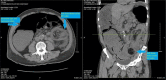

Intussusception is the telescoping of proximal loop of the bowel within distal loop resulting in obliteration of the lumen. Although it frequently occurs with the most common cause of intestinal obstruction in children, it is a rare phenomenon and an uncommon cause of acute intestinal obstruction in adults. Unlike pediatric intussusception, where the cause is idiopathic, adult intussusception is associated with underlying pathology as a lead point. The underlying pathology usually is malignant, but the prognosis is better when there is a benign lead point. The benign lead point intussusceptions are rare and are treated with reduction when there are no signs of ischemia. When there is ischemia or when reduction is not feasible, they are treated with surgical resection. In this report, we describe a rare case of an adult intussusception from a large colonic lipoma in a 79-year-old male, treated successfully with surgical resection.